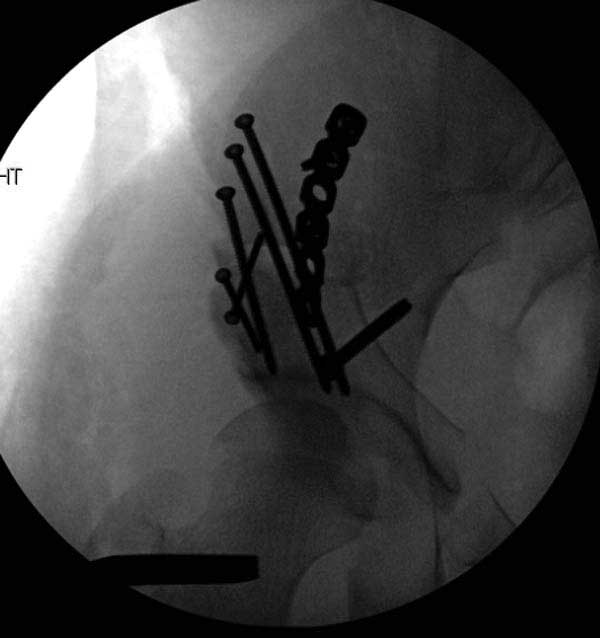

Первым этапом сделана подготовка к ротационной межвертельной остеотомии, затем капсулотомия с удалением импинджмента и периацетабулярная остеотомия с 40 градусной экстензией и операция закончена 35 градусной наружной ротацией бедра. Запланированный варус не сделан из-за относительно нормального покрытия головки.

Одним из преимуществ ПАО является сохранение задней колонны, и всю фиксацию в основном делают спереди из крыла подвздошной кости. При реконструкционных операциях по поводу дисплазии редко коррекция превышает 25 градусов, и достаточной бывает фиксация тремя шурупами вертикально сверху вниз, и один между колоннами спереди кзади. Но у нашего пациента серьезные изменения, и для достижения результата надо было около 40 градусов коррекции, из-за чего в линии остеотомии создалась ступенька. Для предупреждения скольжения дополнительно установлена buttress пластина, которая зафиксирована только в одном сегменте, а другие два шурупа удерживают ASIS. Без остеотомии Anterior Superior Iliac Spine невозможен доступ внутри таза.